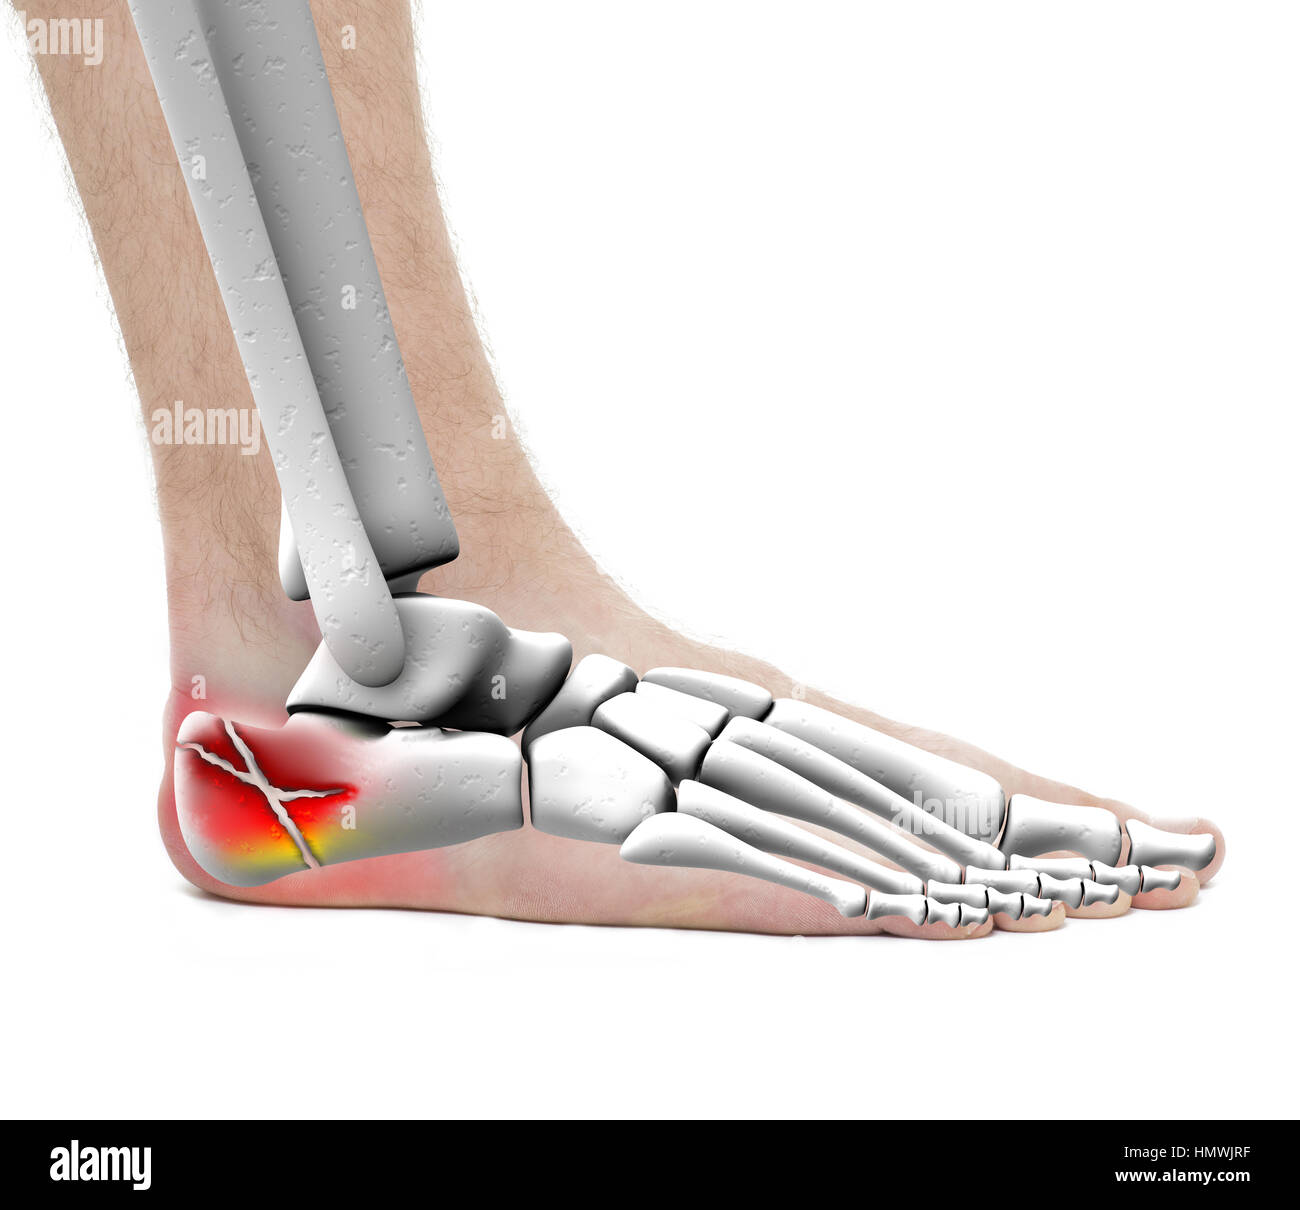

RF2HP0076–OS du pied humain, illustration vectorielle dessinée à la main isolée sur fond blanc, esquisse anatomique en médecine orthopédique

RF2R3WKY1–Illustration médicale des principales parties des os du pied en vue latérale, avec annotations.